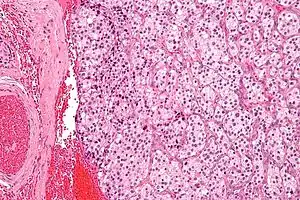

| Micrograph of a carotid body tumor (a type of paraganglioma). | |

On microscopic inspection, the tumor cells are readily recognized. Individual tumor cells are polygonal to oval and are arranged in distinctive cell balls, called Zellballen.[8] These cell balls are separated by fibrovascular stroma and surrounded by sustentacular cells.

By light microscopy, the differential diagnosis includes related neuroendocrine tumors, such as carcinoid tumor, neuroendocrine carcinoma, and medullary carcinoma of the thyroid.

With immunohistochemistry, the chief cells located in the cell balls are positive for chromogranin, synaptophysin, neuron specific enolase, serotonin, neurofilament and Neural cell adhesion molecule; they are S-100 protein negative. The sustentacular cells are S-100 positive and focally positive for glial fibrillary acidic protein. By histochemistry, the paraganglioma cells are argyrophilic, periodic acid Schiff negative, mucicarmine negative, and argentaffin negative.